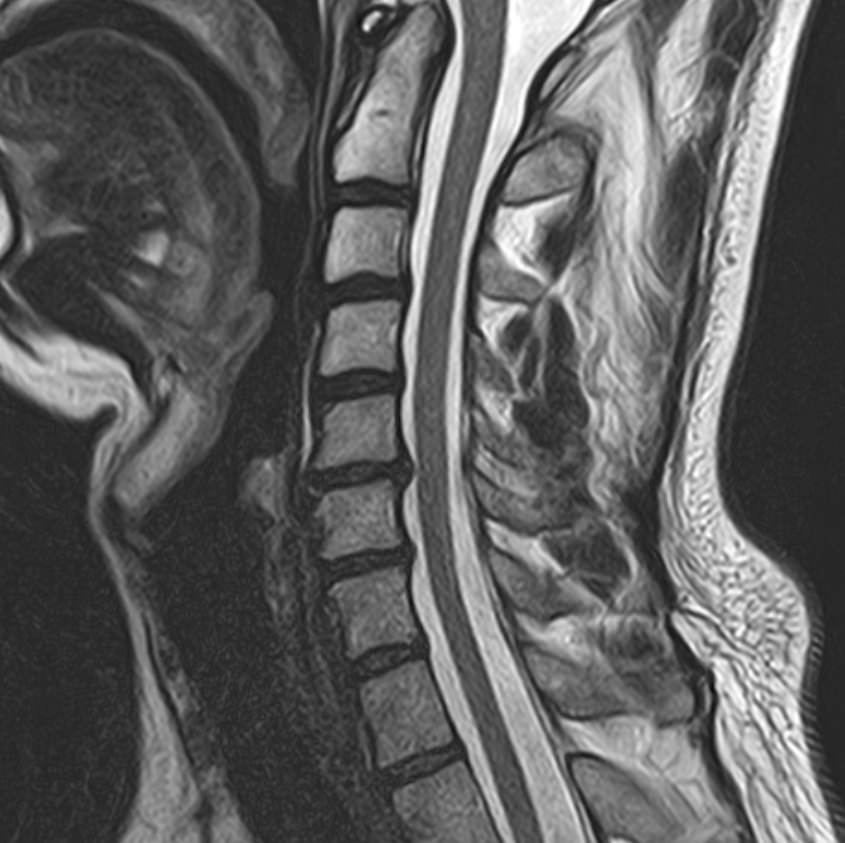

Магнитно-резонансная томография является современным, высокоточным, неинвазивным и безболезненным методом диагностики различной патологии позвоночного столба. Благодаря МРТ можно визуализировать костную структуру позвонков, оценивать состояние спинного мозга на исследуемом уровне, нервных корешков, связочного аппарата и окружающих мягких тканей. В основе метода лежит использование внешнего магнитного поля, которое не оказывает негативного влияния на организм человека. Отсутствие использования ионизирующего излучения делает МРТ безопасным методом исследования и позволяет проводить его достаточно часто по мере необходимости.